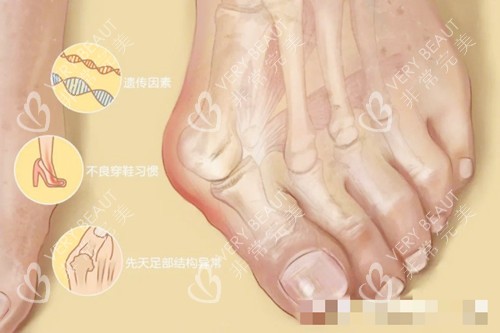

我的拇外翻是"家族遗传病",奶奶和妈妈都有,但我的情况更重的。2015年生完孩子后,脚型像吹气球似的变形,穿38码的鞋都挤得脚趾发紫。去年体检时,医生指着X光片皱眉:"HVA角38度,再不矫正会影响膝盖。"可一想到传统手术要截骨、打钢钉、躺两周,我硬是拖到了今年夏天。

"您这属于复合型拇外翻,伴随前足弓塌陷。"马桂文医生拿着我的3D足部扫描图讲解时,我盯着墙上"26年专注足踝矫正"的锦旗直发怵。他笑着递来光导可视设备的屏幕:"看,这是您增生的骨赘,我们用5D微孔弧技术,通过3毫米的切口就能更准一些祛除。"